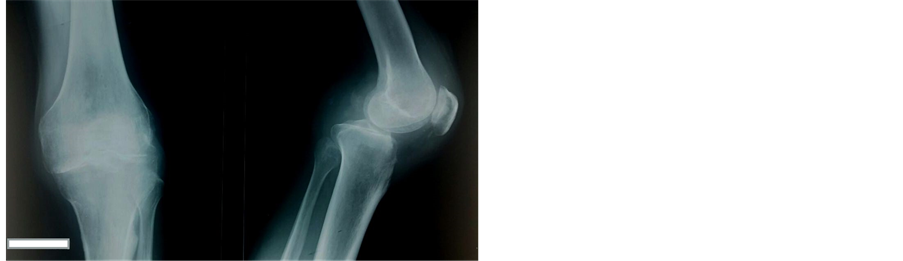

A 73-year-old man consults in our structure for persistent pain and deformation of the lower left leg at the knee for three months after a traffic accident. The patient presents a wound in his left knee that was sutured in the emergency without any radiological assessment; He couldn’t walk or stand for 3 months. Physical examination revealed a deformed left knee in bayonet with antero-posterior enlargement (Figure 1) and a passive flexion of 30˚ and 30˚ to 150˚ of motion without frontal laxity (Figure 2). The extensor mechanisms and the neurovascular functions were all intact. Radiographically, the left knee showed an unreduced posterior dislocation (Figure 3). After detailed explanations of the risks and benefits, a TKA of the left knee was performed. A midline incision using the conventional medial parapatellar approach to the knee was made. Intraoperative examination revealed a fixed posterior dislocation of the knee, and missing osteochondral surfaces over the lower part of the femoral trochlea and anterior tibia plateau and both anterior and posterior cruciate ligaments were absent (Figure 4) with contracture of the posterior soft tissues. Medial-lateral soft tissue balancing was performed first, followed by classical bony cuts at 6˚ anatomical axis. A normal femoral component was chosen after a posterior soft-tissue release for balancing the flexion-extension gaps (the release was not important in the fear to touching the vascular axis). The patella was resurfaced, and posterior soft-tissue release was carried out extensively to allow full extension of the left knee with the components being tested in position. Flexion-extension and medial-lateral gaps were also checked to be nearly in balance, with relative stability during the full range of motion with the prostheses in place. Because stability was obtained using an LPS (Legated postero stabilized) type of implant. A constraining implant was not considered necessary. Finally, Nexgen Fixed-Flex total knee components (LPS type, Zimmer) were applied and fully cemented (Figure 5). The intraoperative range of motion was approximately―10˚ - 160˚ a posterior splint was applied to prevent a dislocation for 4 weeks. No dislocation has been noted and mobility was started in the fifth week without complication. At latest follow-up 1 year postoperatively, the man had a stable left knee with a range of motion of―10˚ - 120˚ and Lysholm à 80. Radiographs showed a well aligned and well fixed total knee prosthesis (Figure 6). The patient was very satisfied with the final outcome.

Figure 3. The left knee showed an unreduced posterior dislocation.